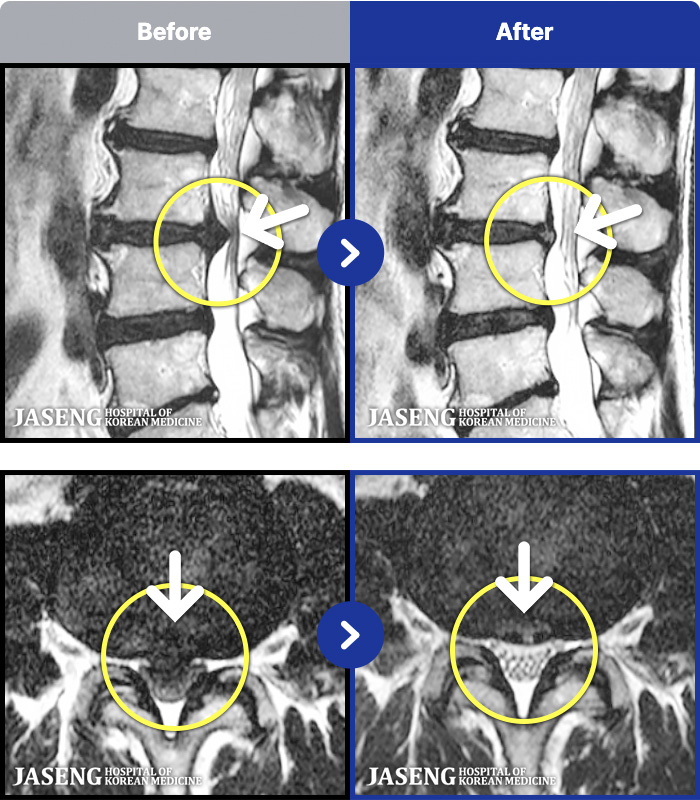

MRI ġ

1,237 MRI ũ ʸ Ȯϼ.

[Ȼ_㸮ũ] 㸮 ְ ٸ ȱⰡ .

[_㸮ũ] 㸮 , ٸ ̾ ϼ̽ϴ.

[õ_㸮ũ] ߲ 㸮 , ٷ

[ϻ_㸮ũ] ݺ ӵǸ ڼ ÿ ȭǴ ߵ ̻ ȣϴ ¿ϴ.

[ϻ_㸮ũ] ؽϰ ߰ ̴ · ϻȰ ¿ϴ.

[ؿ_㸮ũ] 㸮 ϰ

[_㸮ũ] 㸮 ߰ Ͽ ϼ̽ϴ.

[_㸮ũ] Ƹ ߱ ̾ ϼ̽ϴ.

[_㸮ũ] 㸮 ݱ , ٸ Ͽ ϼ̽ϴ.